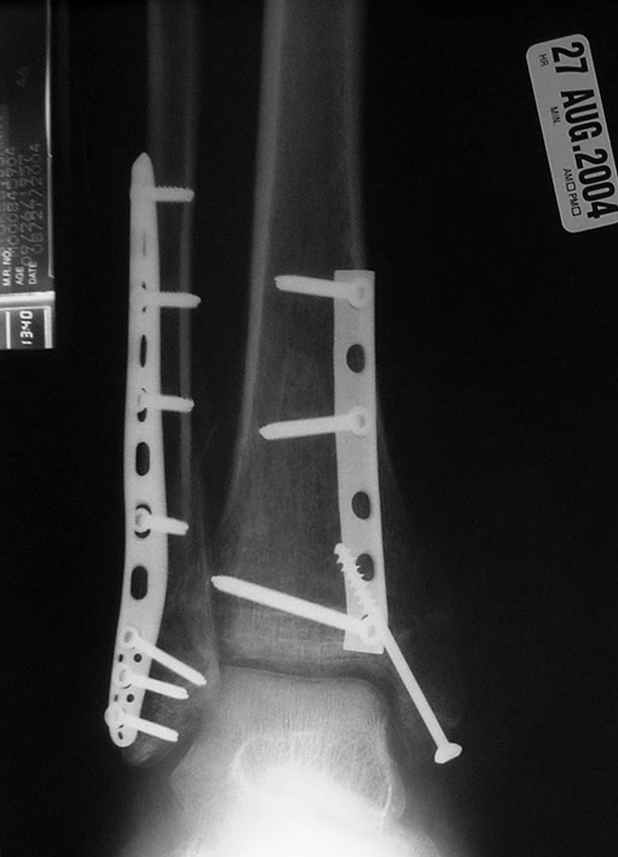

Re: ANKLE FRACTURE

Второй случай сделан из одного разреза